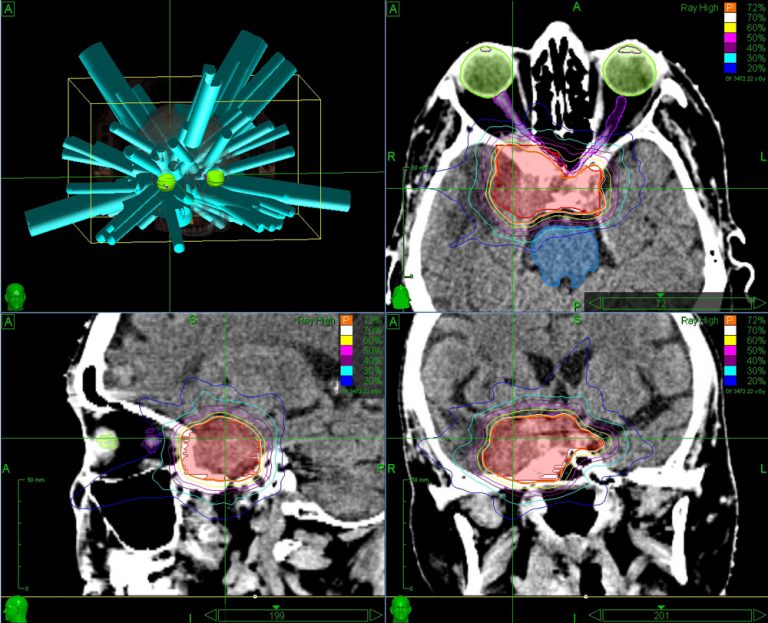

Treatment planning of hypofractionated stereotactic radiosurgery (HSRS

Treatment planning of hypofractionated stereotactic radiosurgery (HSRS Radiosurgery Brain It is a common treatment for brain and spinal cord tumours. These side effects usually improve a few. It may be used to treat secondary brain tumours (brain. Stereotactic radiosurgery (srs) is a very precise treatment to a small area of the brain. The treatment aims to give a high dose to small,. Stereotactic radiosurgery (srs) is a specialised way. Radiosurgery Brain.